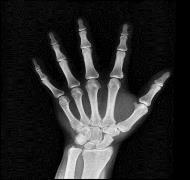

For testing, grayscale and color photos are obtained. The simulations are run on MATLAB R2021b with a Windows 10 operating system and 8 GB of memory. The test images are shown in Figure 6(a) to Figure 6(f). As a result, these cipher images provide no relevant information about the plain image. The plain images retrieve as it is after the decryption process. As we can see, our scheme can be implemented quickly. Table 1 shows the results of evaluation metrics between input and cipher image and time of encryption. Table 2 shows the results of evaluation metrics between the input image and retrieved image and the time of decryption. The tables display the results of the encryption and decryption of each image using three chaotic maps, to compare these results later and to determine the best map in the case of encryption and decryption.

(a) (b) (c) (d) (e) (f) Figure 6. Plain grayscale images with different sizes: (a) 512×512, (b) 600×600, (c) 900×900, (d) 1024×1024, (e) 612×612, and (f) 500×500